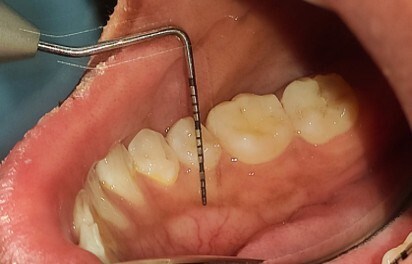

The MGJ was delineated by the visual method and the roll method following clinical examination in dental chairs appropriately equipped. Visual assessment relies on identifying the color difference between the gingiva and alveolar mucosa. The mucosa beyond the MGJ typically appears darker red compared to the AG, helping to demarcate the MGJ. The rolling probe method entails pushing the neighboring alveolar mucosa coronally with the blunt end of a probe. It is a functional assessment method that aids in determining the boundary between gingiva and movable mucosa.10 The probing sulcus depth was subtracted from the measured KG width at the mid-lingual aspect of each tooth to determine the width of AG, and all fractional measurements were rounded off to the nearest whole number of millimeters (Figure 1 through Figure 3).

Fig 3 = determining width of keratinized gingiva.

Figure 3